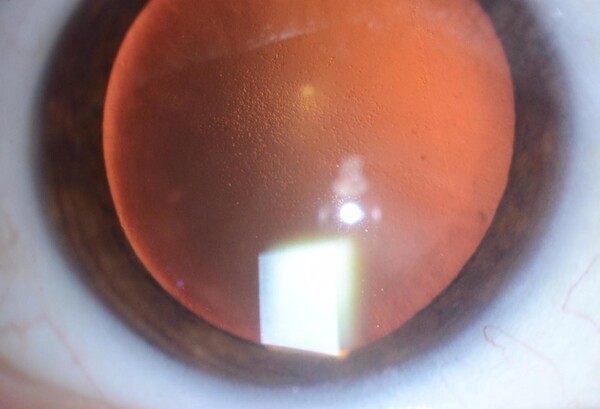

Edema Corneal

La función del endotelio es, a grandes rasgos, mantener el estroma corneal ‘’seco’’, deshidratado. Cuando el estroma está deshidratado, la disposición de las fibras de colágeno permite que el tejido sea transparente. Cuando el estroma se llena de líquido, esa disposición de fibras de colágeno se altera en el espacio y el tejido se opaca. Algunas enfermedades, como la distrofia de Fuchs, generan una pérdida de células endoteliales más acelerada de lo habitual. Por otro lado, cualquier cirugía intraocular, las inflamaciones intraoculares y el glaucoma también pueden generar una aceleración en la perdida de estas células.

Cuando se pierde un número crítico de estas células endoteliales, el endotelio como un todo empieza a ser incapaz de mantener deshidratada la córnea y empieza a haber edema (líquido) en el espesor de la córnea. Al llenarse el estroma corneal de líquido, la córnea pierde transparencia. Al comienzo de la enfermedad endotelial, el edema suele ser mayor por la mañana, dando visión borrosa que dura alguna/s hora/s y luego mejora con el correr del día. A medida que empora la función endotelial, el edema se hace cada vez mayor, y proporcionalmente progresa la opacidad corneal.